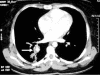

Hughes-Stovin Syndrome (HSS) is a very rare clinical disorder characterized by thrombophlebitis and multiple pulmonary and/or bronchial aneurysms. Less than 40 published cases of HSS have been described in English medical literature so far. The exact etiology and pathogenesis of HSS is unknown; possible causes include infections and angiodysplasia. HSS has also been considered as a variant of Behcet's disease (BD). Patients with HSS usually present with cough, dyspnea, fever, chest pain and haemoptysis. The management of HSS can either be medical or surgical. Medical management includes the use of steroids and cytotoxic agents. Cyclophosphamide, in particular, is a favored therapeutic agent in this regard. Antibiotics have no proven role in HSS while anticoagulants and thombolytic agents are generally contraindicated due to an increased risk of fatal hemorrhage. However, their use may be considered with great care under special circumstances, for instance, intracardiac thrombi or massive pulmonary embolism. For cases of massive hemoptysis due to large pulmonary aneurysms or those with lesions confined to one segment or one lung, lobectomy or pneumectomy can be carried out. However, surgical risks merit serious consideration and must be discussed with the patient. Transcatheter arterial embolization has emerged as a less invasive alternative to surgery in selected cases of HSS. Overall, patients with HSS have a poor prognosis and aneurysmal rupture is the leading cause of death. However, early diagnosis and timely intervention is crucial in improving the prognosis. There is a need to clearly elucidate the genetic, etiologic and pathologic basis for HSS in the future. Although most of the evidence put forward to refute the role of an infectious agent in the etiology and pathogenesis of HSS is based on negative blood and other body fluid cultures, more robust objective assessment is needed through the use of electron microscopy or 16 sRNA studies. The development of better therapeutic agents is also needed to address and prevent the serious consequences arising from pulmonary arterial aneurysms seen in BD and HSS. Also, the issue of anticoagulation in these patients is challenging and requires further deliberation.